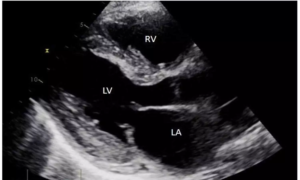

High urea levels associated with increased left ventricular hypertrophy risk, suggests study

Wantai Dang and team from the First Affiliated Hospital of Chengdu…